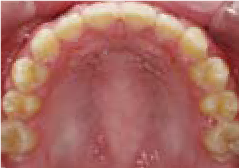

さらに、上からあごの骨を見たところ、中央がくびれた“ひょうたん型”に変形しており、あごの成長にも偏りが見られました。